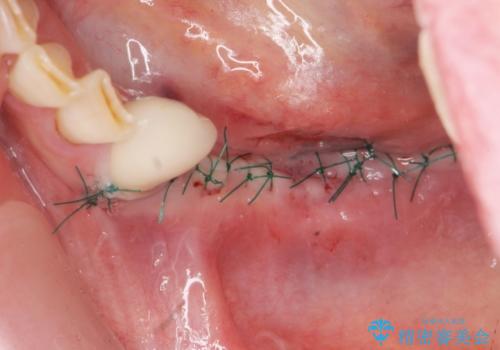

- 外科手術のため、術後に痛みや腫れ、違和感を伴います

- メンテナンスを怠ったり喫煙により、お口の中に大きな悪影響を及ぼすインプラント周囲炎等にかかる可能性があります